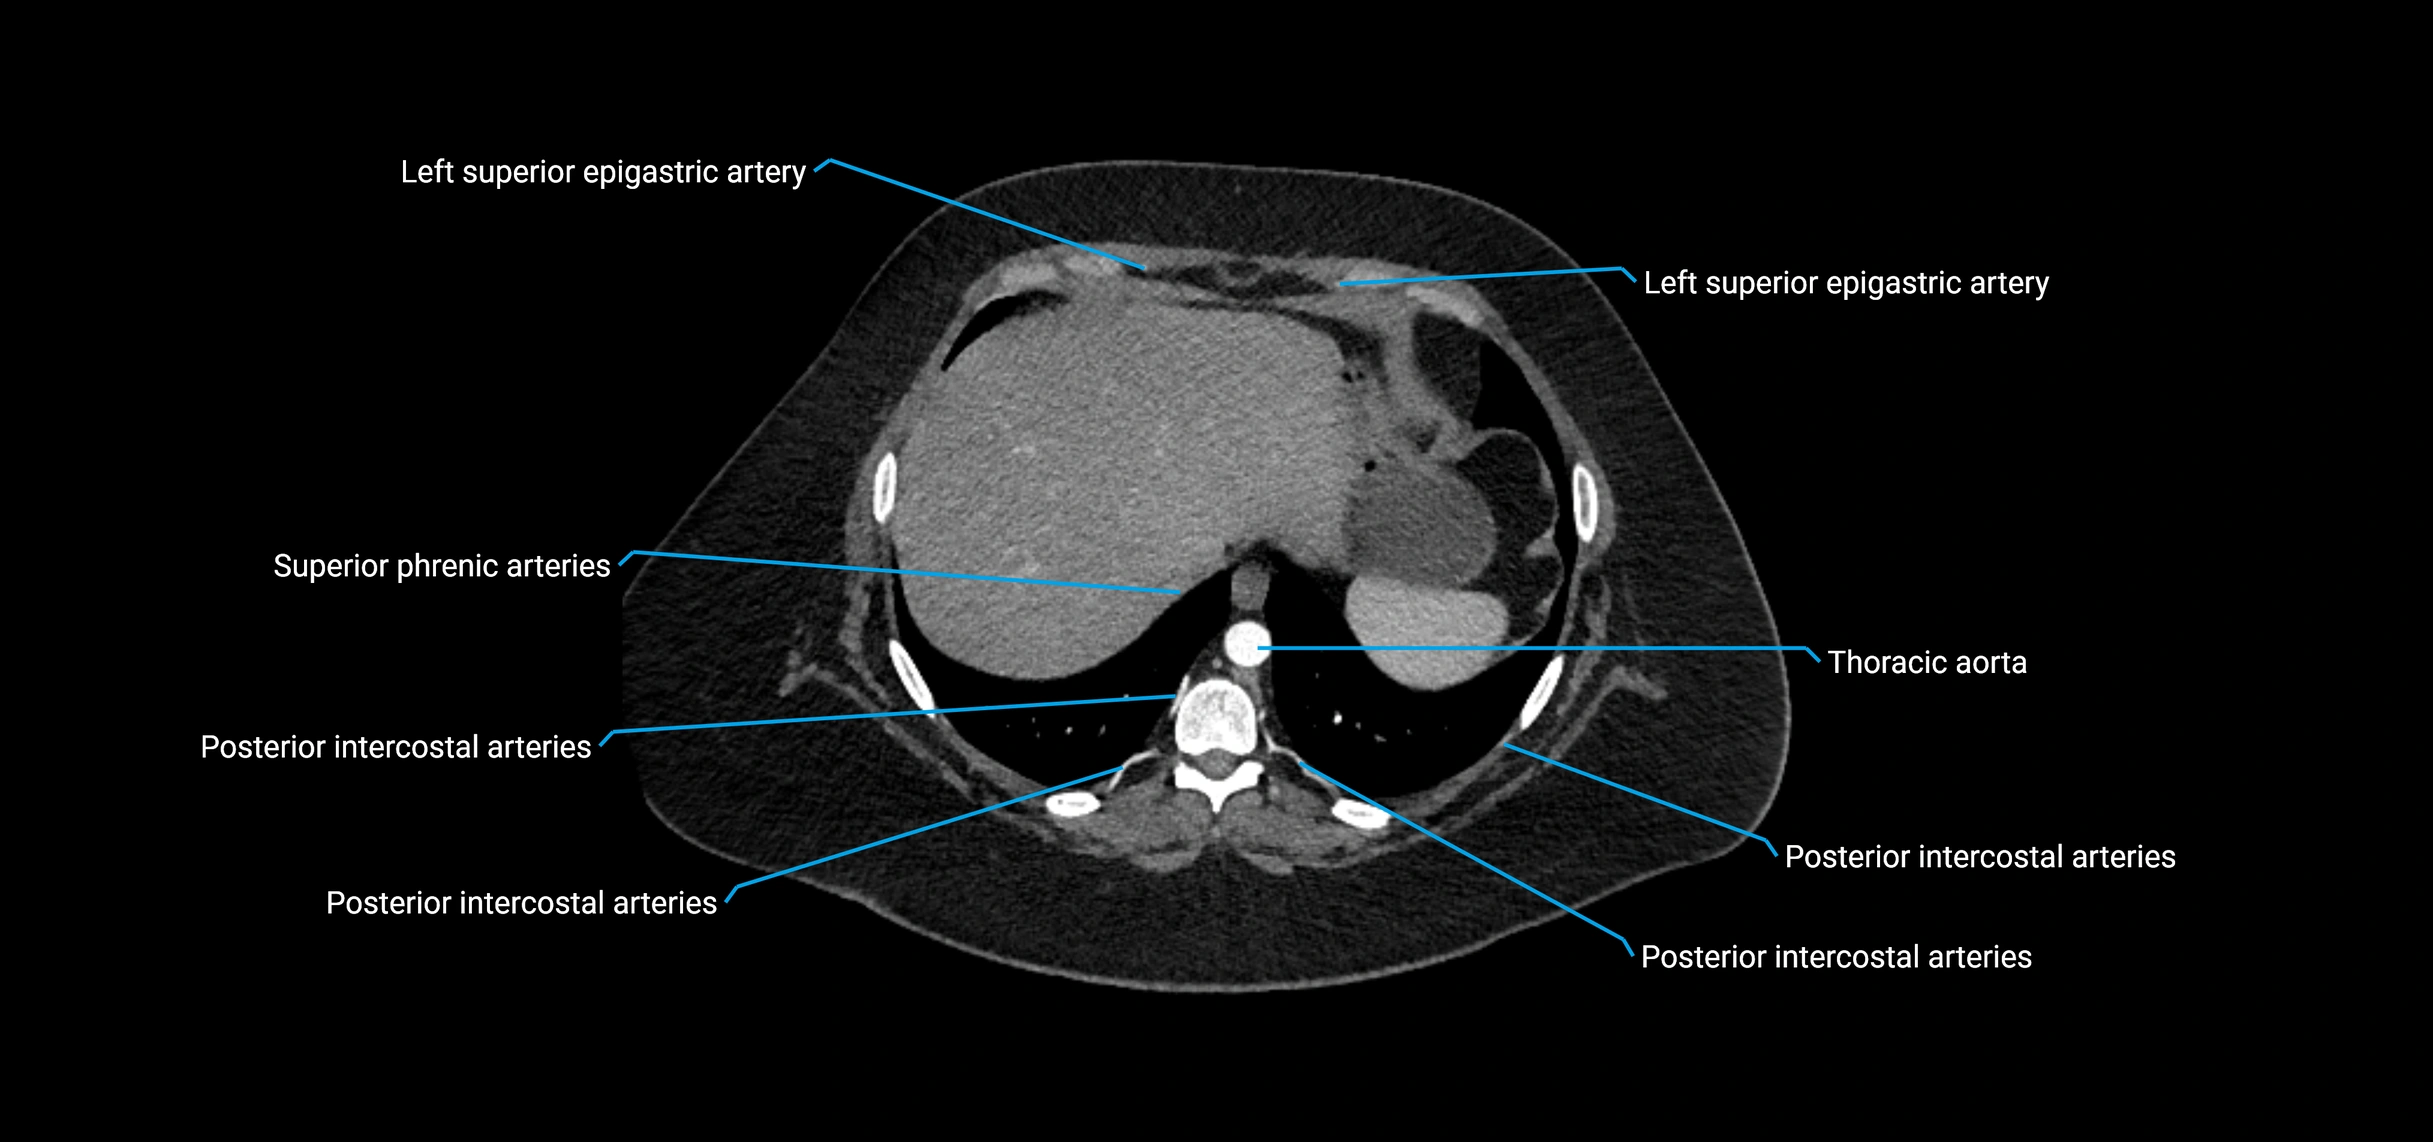

CT Appearance

Non-contrast CT:

• Appears as a tubular soft tissue structure anterior to vertebral bodies

• Calcified atherosclerotic plaques appear as hyperdense foci along the wall

• Useful for screening abdominal aortic aneurysm (AAA) size and mural calcification